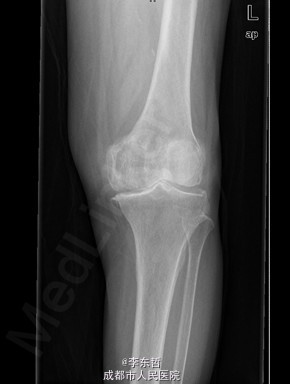

患者女,74岁,因“双膝疼痛20年,加重伴行走困难8年”入院。患者诉20年前开始出现双膝关节疼痛,负重行走、下楼时疼痛加重,休息后可缓解,尚可下蹲。自行购买止痛药口服,关节腔内注射玻璃酸钠、理疗等处理,疼痛时有缓解。但症状反复发作。8年前疼痛加重且行走困难,扶拐行走仅能坚持约10余米,上下楼梯艰难,下蹲不能,以左侧为重。遂来院就诊。

查体:跛行步态,双膝关节屈曲内翻畸形,双膝内侧间隙压痛,双膝髌股关节间隙压痛,左膝伸-20°,屈110°内翻10°。右膝伸-20°,屈110°内翻10°,双膝屈伸活动时髌骨下摩擦感(+)。 辅助检查:X片示双侧髌股关节内侧间室变窄,关节边缘骨赘增生,软骨下骨硬化。

入院诊断:1、左膝骨关节炎伴屈曲内翻畸形; 2、右膝骨关节炎伴屈曲内翻畸形; 诊疗计划:1、向患者及家属交待病情及注意事项。2、向上级医生汇报患者病情。3、完善相关术前检查;4、择期手术。